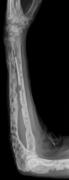

Medical imaging

The diagnostic examination of a person with suspected multiple myeloma typically includes a skeletal survey. This is a series of X-rays of the skull, axial skeleton, and proximal long bones. Myeloma activity sometimes appears as "lytic lesions" (with local disappearance of normal bone due to resorption). And on the skull X-ray as "punched-out lesions" (pepper-pot skull). Lesions may also be sclerotic, which is seen as radiodense.[52] Overall, the radiodensity of myeloma is between −30 and 120 Hounsfield units (HU).[53] Magnetic resonance imaging is more sensitive than simple X-rays in the detection of lytic lesions, and may supersede a skeletal survey, especially when vertebral disease is suspected. Occasionally, a CT scan is performed to measure the size of soft-tissue plasmacytomas. Bone scans are typically not of any additional value in the workup of people with myeloma (no new bone formation; lytic lesions not well visualized on bone scan).